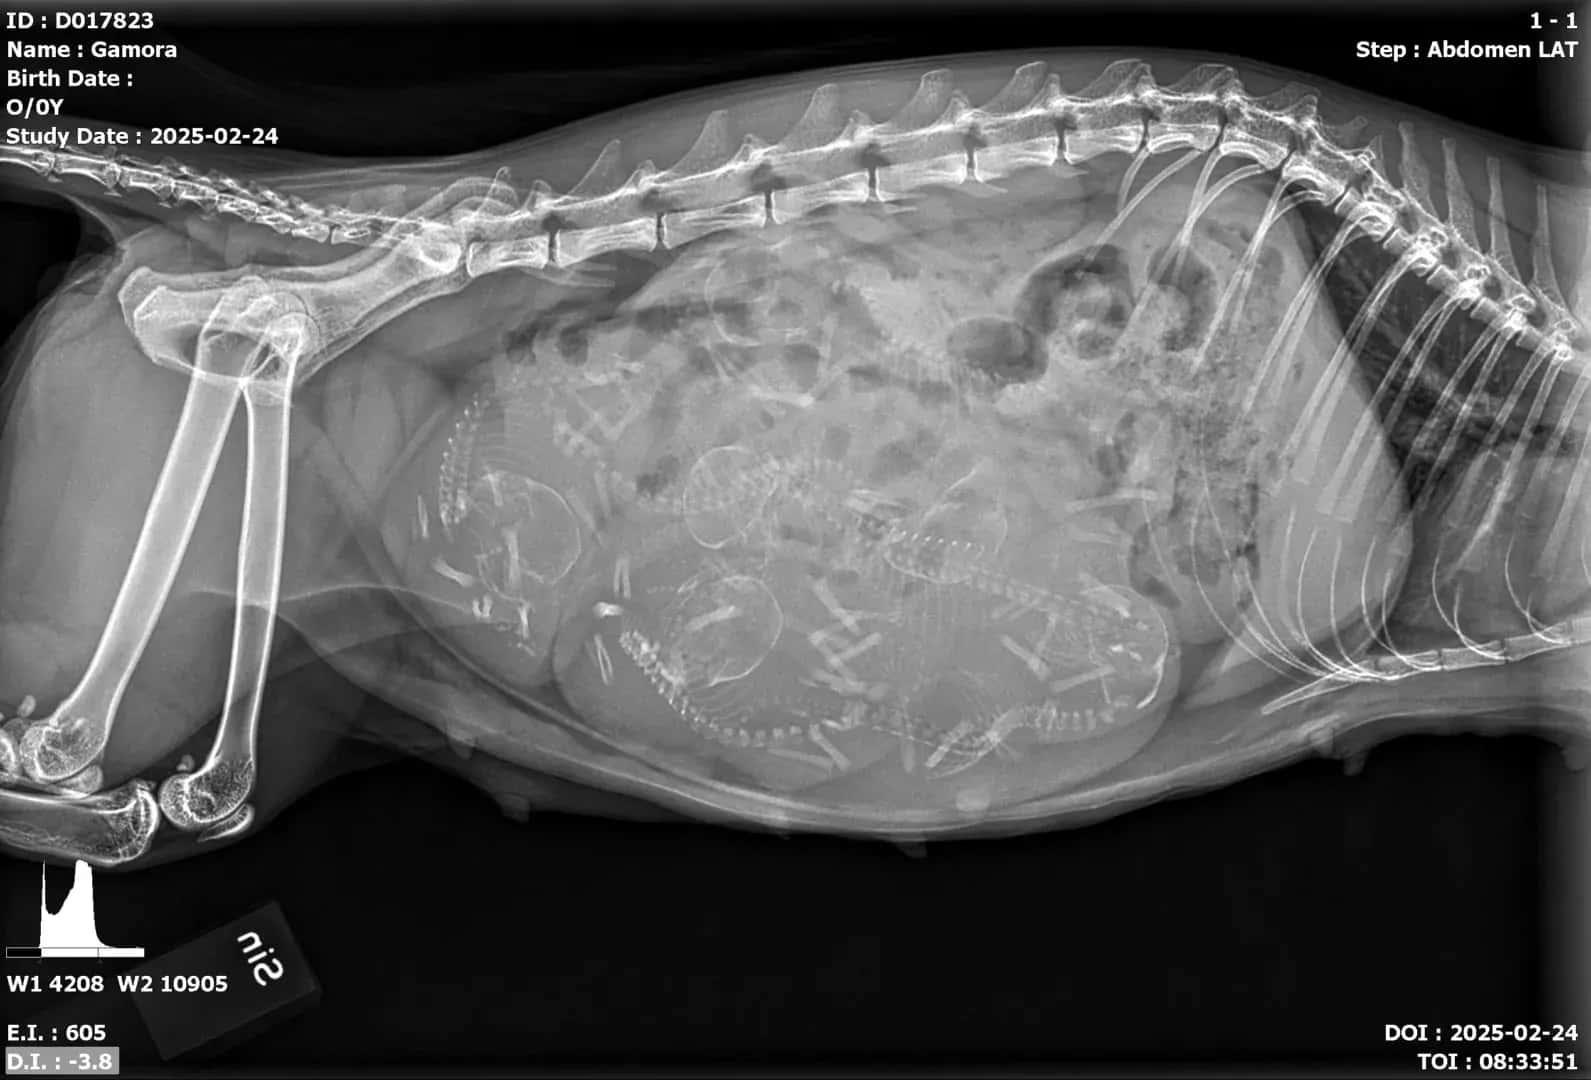

Gamora väntar sin 4’e kull här i början av Mars månad